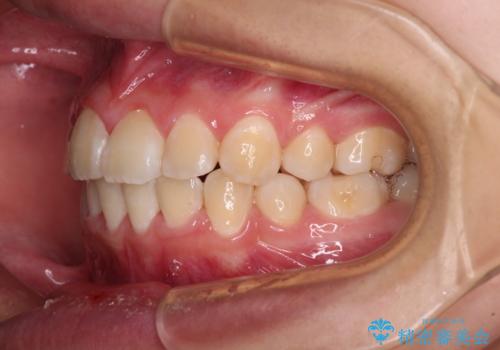

八重歯で正中が右にずれている ワイヤー装置での抜歯矯正で正中位置を改善

- 上下の八重歯と前歯のデコボコを気にして来院された患者様です。

右上の八重歯が特に著しく、上顎正中が右側にシフトしていました。

デコボコが強いため小臼歯4本を抜歯し、上顎正中を左側に移動させるために補助装置を使用して、ワイヤー装置にて矯正治療を行うこととしました。